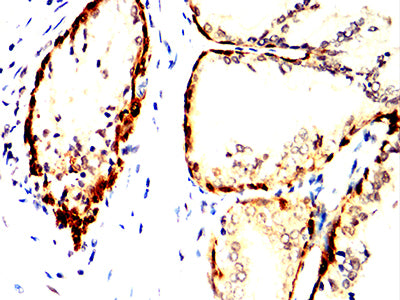

- Immunohistochemical analysis of paraffin-embedded human prostate cancer tissues using ACHE mouse mAb with DAB staining.